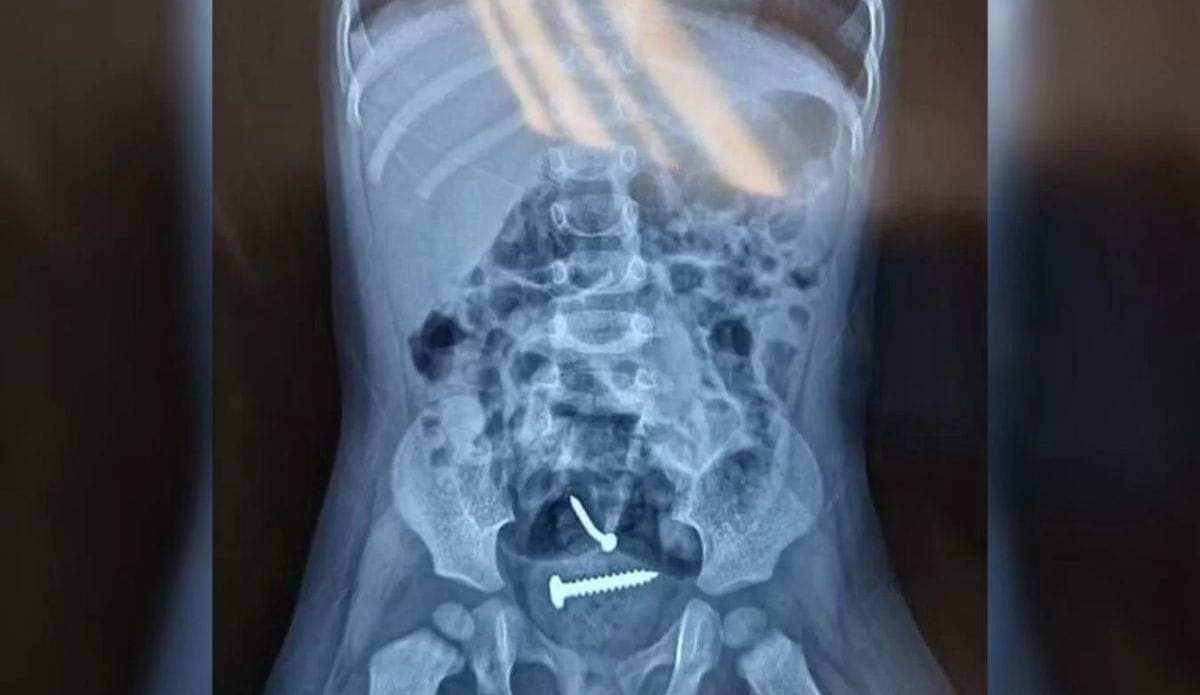

Conforme o Metrópoles, a vítima e a mãe oram encontradas em um terreno, e encaminhadas para o hospital e, após a realização dos exames, um raio-X apontou a presença de objetos estranhos dentro do corpo da menina. Ela também tinha lesões nas partes íntimas.